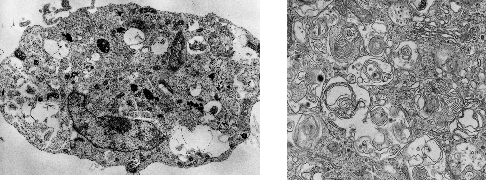

アポトーシスを起こしにくい細胞株(Bax/Bak欠損細胞)に抗癌剤などのアポトーシス刺激を加えると、オートファジー(自食反応)に依存した細胞死機構が活性化し、その結果細胞は死に至ることを、我々は世界に先駆けて見出した(Nature Cell Biol., 2004) (図2)。オートファジー様細胞死 (autophagic cell death)は、生理的な細胞死や病理的な細胞死に関与することが示唆されており、現在その詳細な分子機構の解析を行っている。

図2.抗がん剤によって誘導されたオートファジー様細胞死